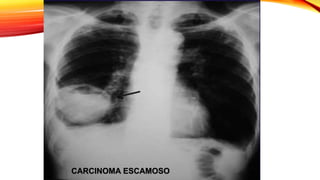

Carcinoma escamoso

Representa el 30% de los TU malignos de pulmón

Esta fuertemente relacionado con el tabaco (90%)

Suelen originarse en los bronquios principales y su

crecimiento es lento.

Produce una marcada respuesta en el tejido pulmonar

del huésped con presencia de infiltrados

linfoplasmocitarios y células histocitarias gigantes

multinucleadas

• Masa central de gran tamaño que a menudo se cavita.